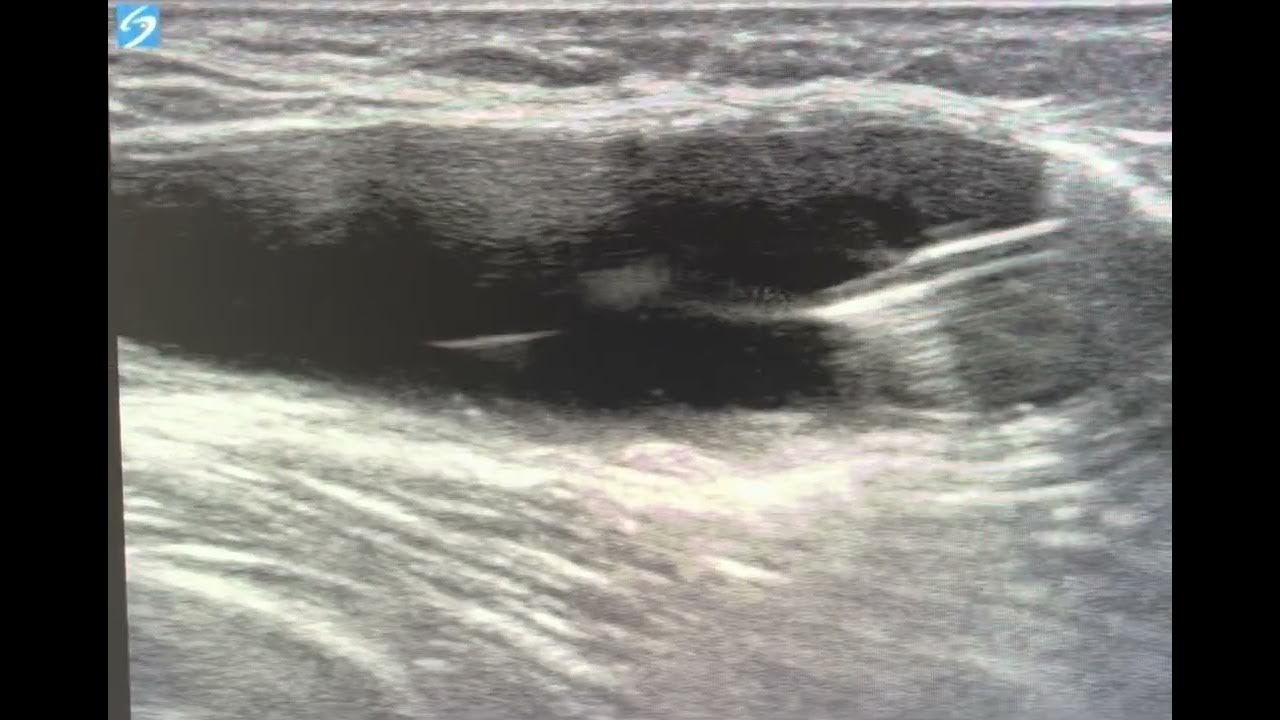

From www.youtube.com

Ultrasound guided popliteal cyst (Baker's cyst) aspiration and steroid injection YouTube Baker's Cyst Aspiration Cpt Code Which cpt code applies to aspiration of a baker's cyst? for symptomatic relief, a baker’s cyst can be aspirated, with or without concomitant corticosteroid injection into the cyst. if the aspiration of the cyst in the knee was performed arthroscopically i believe you would use the unlisted. what is the correct cpt code for injection/aspiration of a. Baker's Cyst Aspiration Cpt Code.

ultrasound guided baker's cyst aspiration YouTube Baker's Cyst Aspiration Cpt Code For the calf aspiration, i would assign cpt code 10160. I have read that 20612 is not appropriate. what is the correct cpt code for injection/aspiration of a baker's cyst? if the aspiration of the cyst in the knee was performed arthroscopically i believe you would use the unlisted. cpt code 20612 should be used when performing. Baker's Cyst Aspiration Cpt Code.